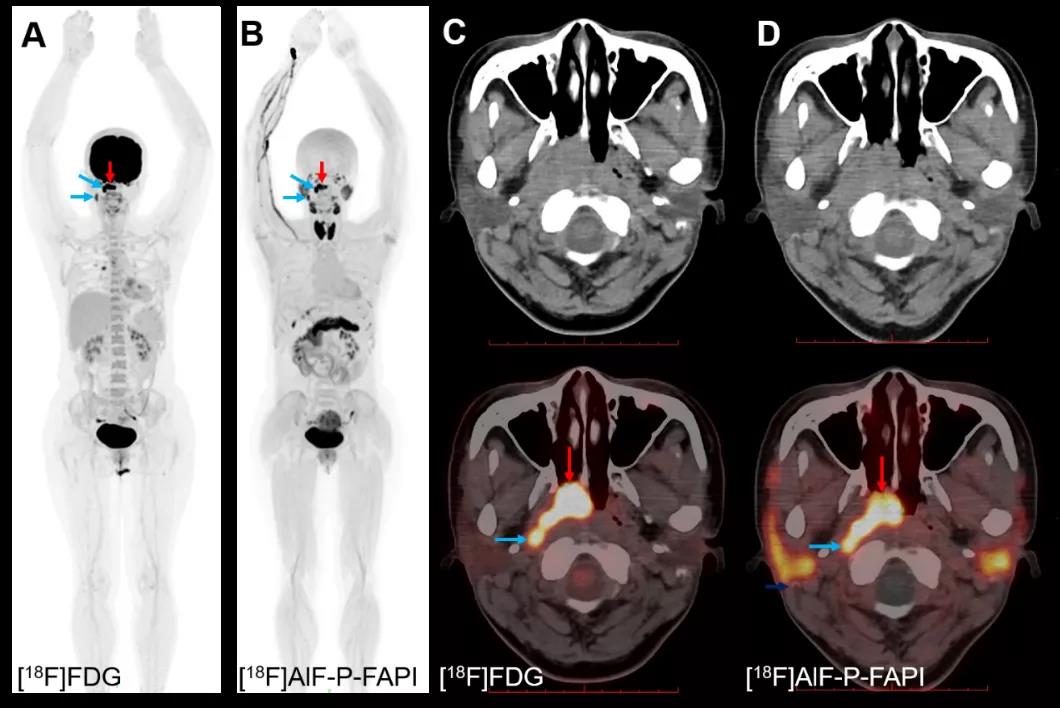

该研究设计了一种新型针对成纤维细胞活化蛋白(Fibroblast activation protein,FAP)的示踪剂,与国外报道的FAP示踪剂进行临床前体内外比较,并对1名鼻咽癌患者进行PET/CT成像,结果显示,化学改构提高了探针在病灶的摄取值和滞留时间,清晰显示出鼻咽癌患者的原发肿瘤和淋巴结转移。

因此,进一步发展和优化核素标记的FAP示踪剂对广义纤维化疾病的诊断和治疗至关重要。近年来已报道的几种68Ga或18F标记的FAP示踪剂(图1)对FAP相关的疾病具有显像价值,但都存在着体内清除快、病灶中滞留时间短等问题。本文研制的新型FAP示踪剂[18F]AlF-P-FAPI具有病灶摄取值高、滞留时间长和体内稳定等优点,且自动化制备简便和放射化学产率高。初步临床试验证实,其对人体显像安全可行。因此,[18F]AlF-P-FAPI是一种有前途的核素显像剂,具有进一步扩大临床适应症研究的价值。

[18F]AlF-P-FAPI和[18F]FDG对鼻咽癌患者PET/CT显像图